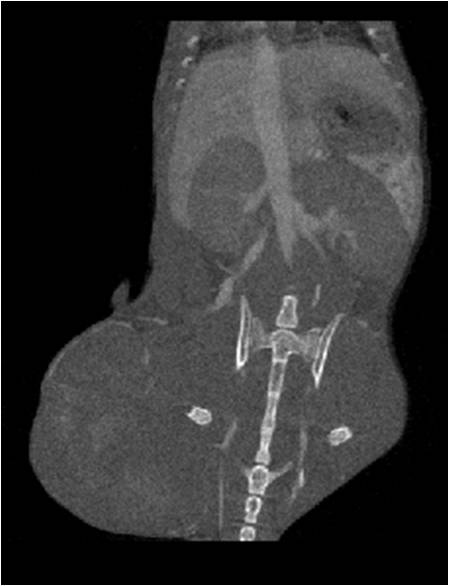

腫瘤血管生成

肺轉移

小鼠模式,22.5μm像素

正常

8天 14天

無造影劑注入 造影劑注入